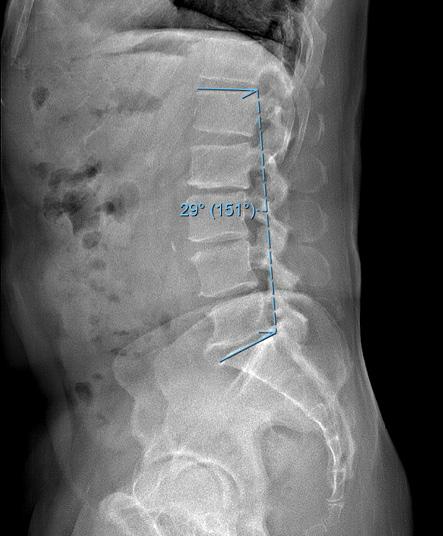

Figure. (A) Preoperative and (B) 6-month postoperative lateral radiographs demonstrating change in lumbar lordosis after isolated decompression.

Madkouri et al also showed severe preoperative imbalance, SVA greater than 100 mm, was predictive of persistent imbalance after surgery.17 Salimi et al similarly reported longer term alignment outcomes after isolated decompression, also finding that LL significantly increased while SVA decreased at 2 and 5 years postoperatively. 9 Overall, 42.6% of patients with preoperative malalignment developed normal alignment postoperatively, maintaining proper alignment up to the 5-year follow-up. In this cohort, postoperative malalignment was associated with significantly worse VAS back pain scores at long-term follow-up. These findings are consistent with those of Hikata et al and Ogura et al, who reported similarly sustained transitions to improved sagittal alignment following isolated decompression of 52.3% and 44.8%, respectively, at 2-year follow-up. 12,13 Ogura et al further reported that continued positive postoperative SVA had negative implications on clinical outcomes and patient-reported quality of life. Along with improvements in sagittal alignment, Bouknaitir et al found significant concomitant reductions in PI-LL at 6-month follow-up, which

was further studied by Minamide et al and Chang’s report of LSS patients being more likely to have satisfactory clinical outcomes with decompression alone if the PI-LL mismatch is minimized. 18–20 A separate analysis by Chang demonstrated a correlation of 10° increase in lumbar lordosis after decompression surgery was associated with a 5-point improvement in physical function scores. 21